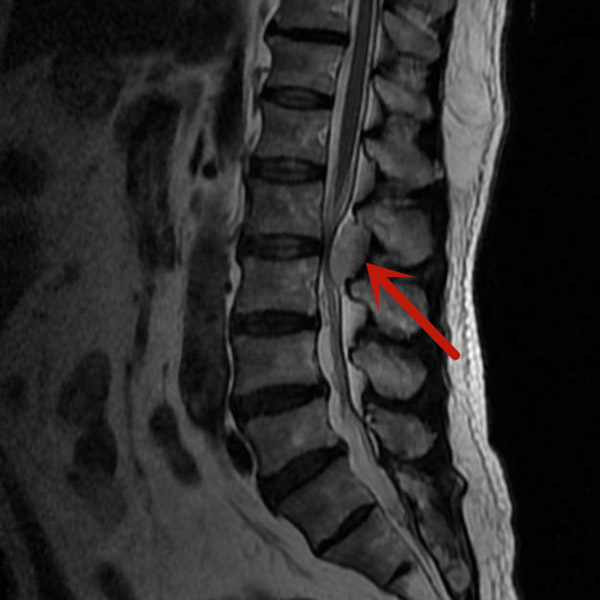

梁先生因雙下肢麻木來我院就診,經磁共振檢查發現是腰椎管內血管瘤在作怪,若不及時手術治療,隨著腫瘤的生長、神經長時間受壓,將可能導致雙下肢癱瘓、大小便失禁等嚴重后果。

經我院脊柱外科醫療團隊研究后,決定對梁先生實施內鏡下腰椎管內腫瘤切除術,腫瘤約3.5cm×1.5cm大小,別看腫瘤不大,但要完全通過0.8cm大小切口在內鏡下切除,腫瘤后方的椎板切除減壓、腫瘤與周圍神經的分離、腫瘤的暴露、腫瘤的徹底切除,這都需要嫻熟的內鏡操作技術。

在完善術前檢查,排除手術禁忌,充分做好術前準備后,由微創手術經驗豐富的醫師主刀,經過兩個小時,完整將腫瘤切除。梁先生術后第一天便可下床活動,四天后即康復出院。